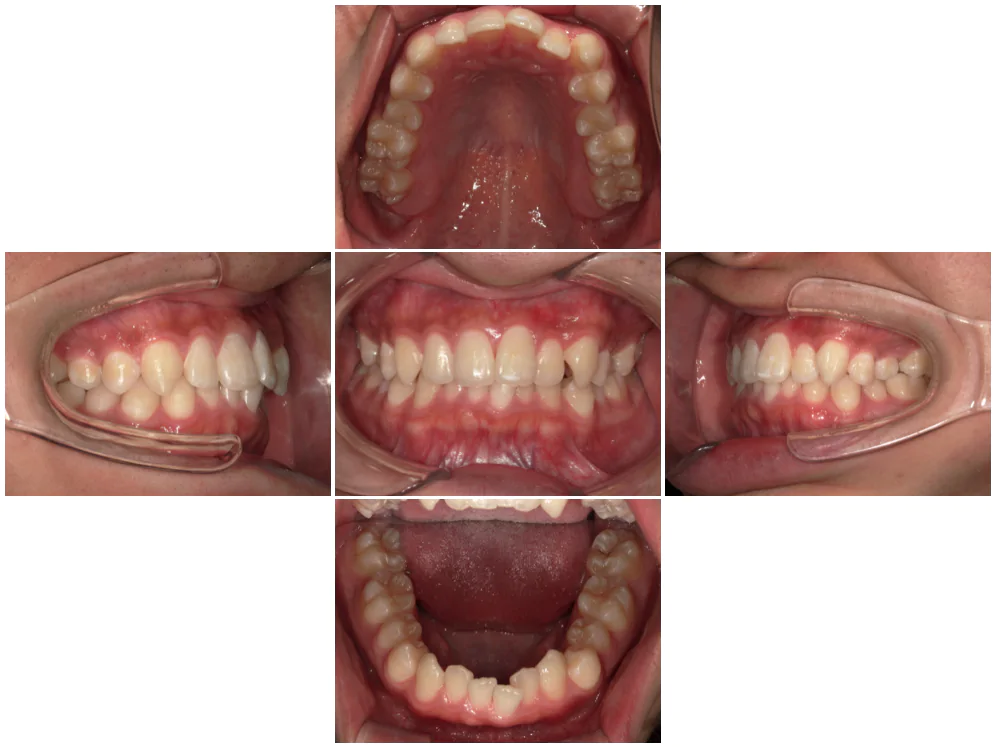

症例4

| 来院時の主訴 | 全体的なガタガタ |

| 医院での対応や適用装置 | マウスピース矯正装置を使用して主訴である |

| 通院期間 | 11ヶ月 |

| 通院回数 | 5回 |

| 治療費用総額 | 852,500円(税込) |

| リスクと副作用 | 矯正治療による歯の移動に伴う痛み、歯根吸収、虫歯 |